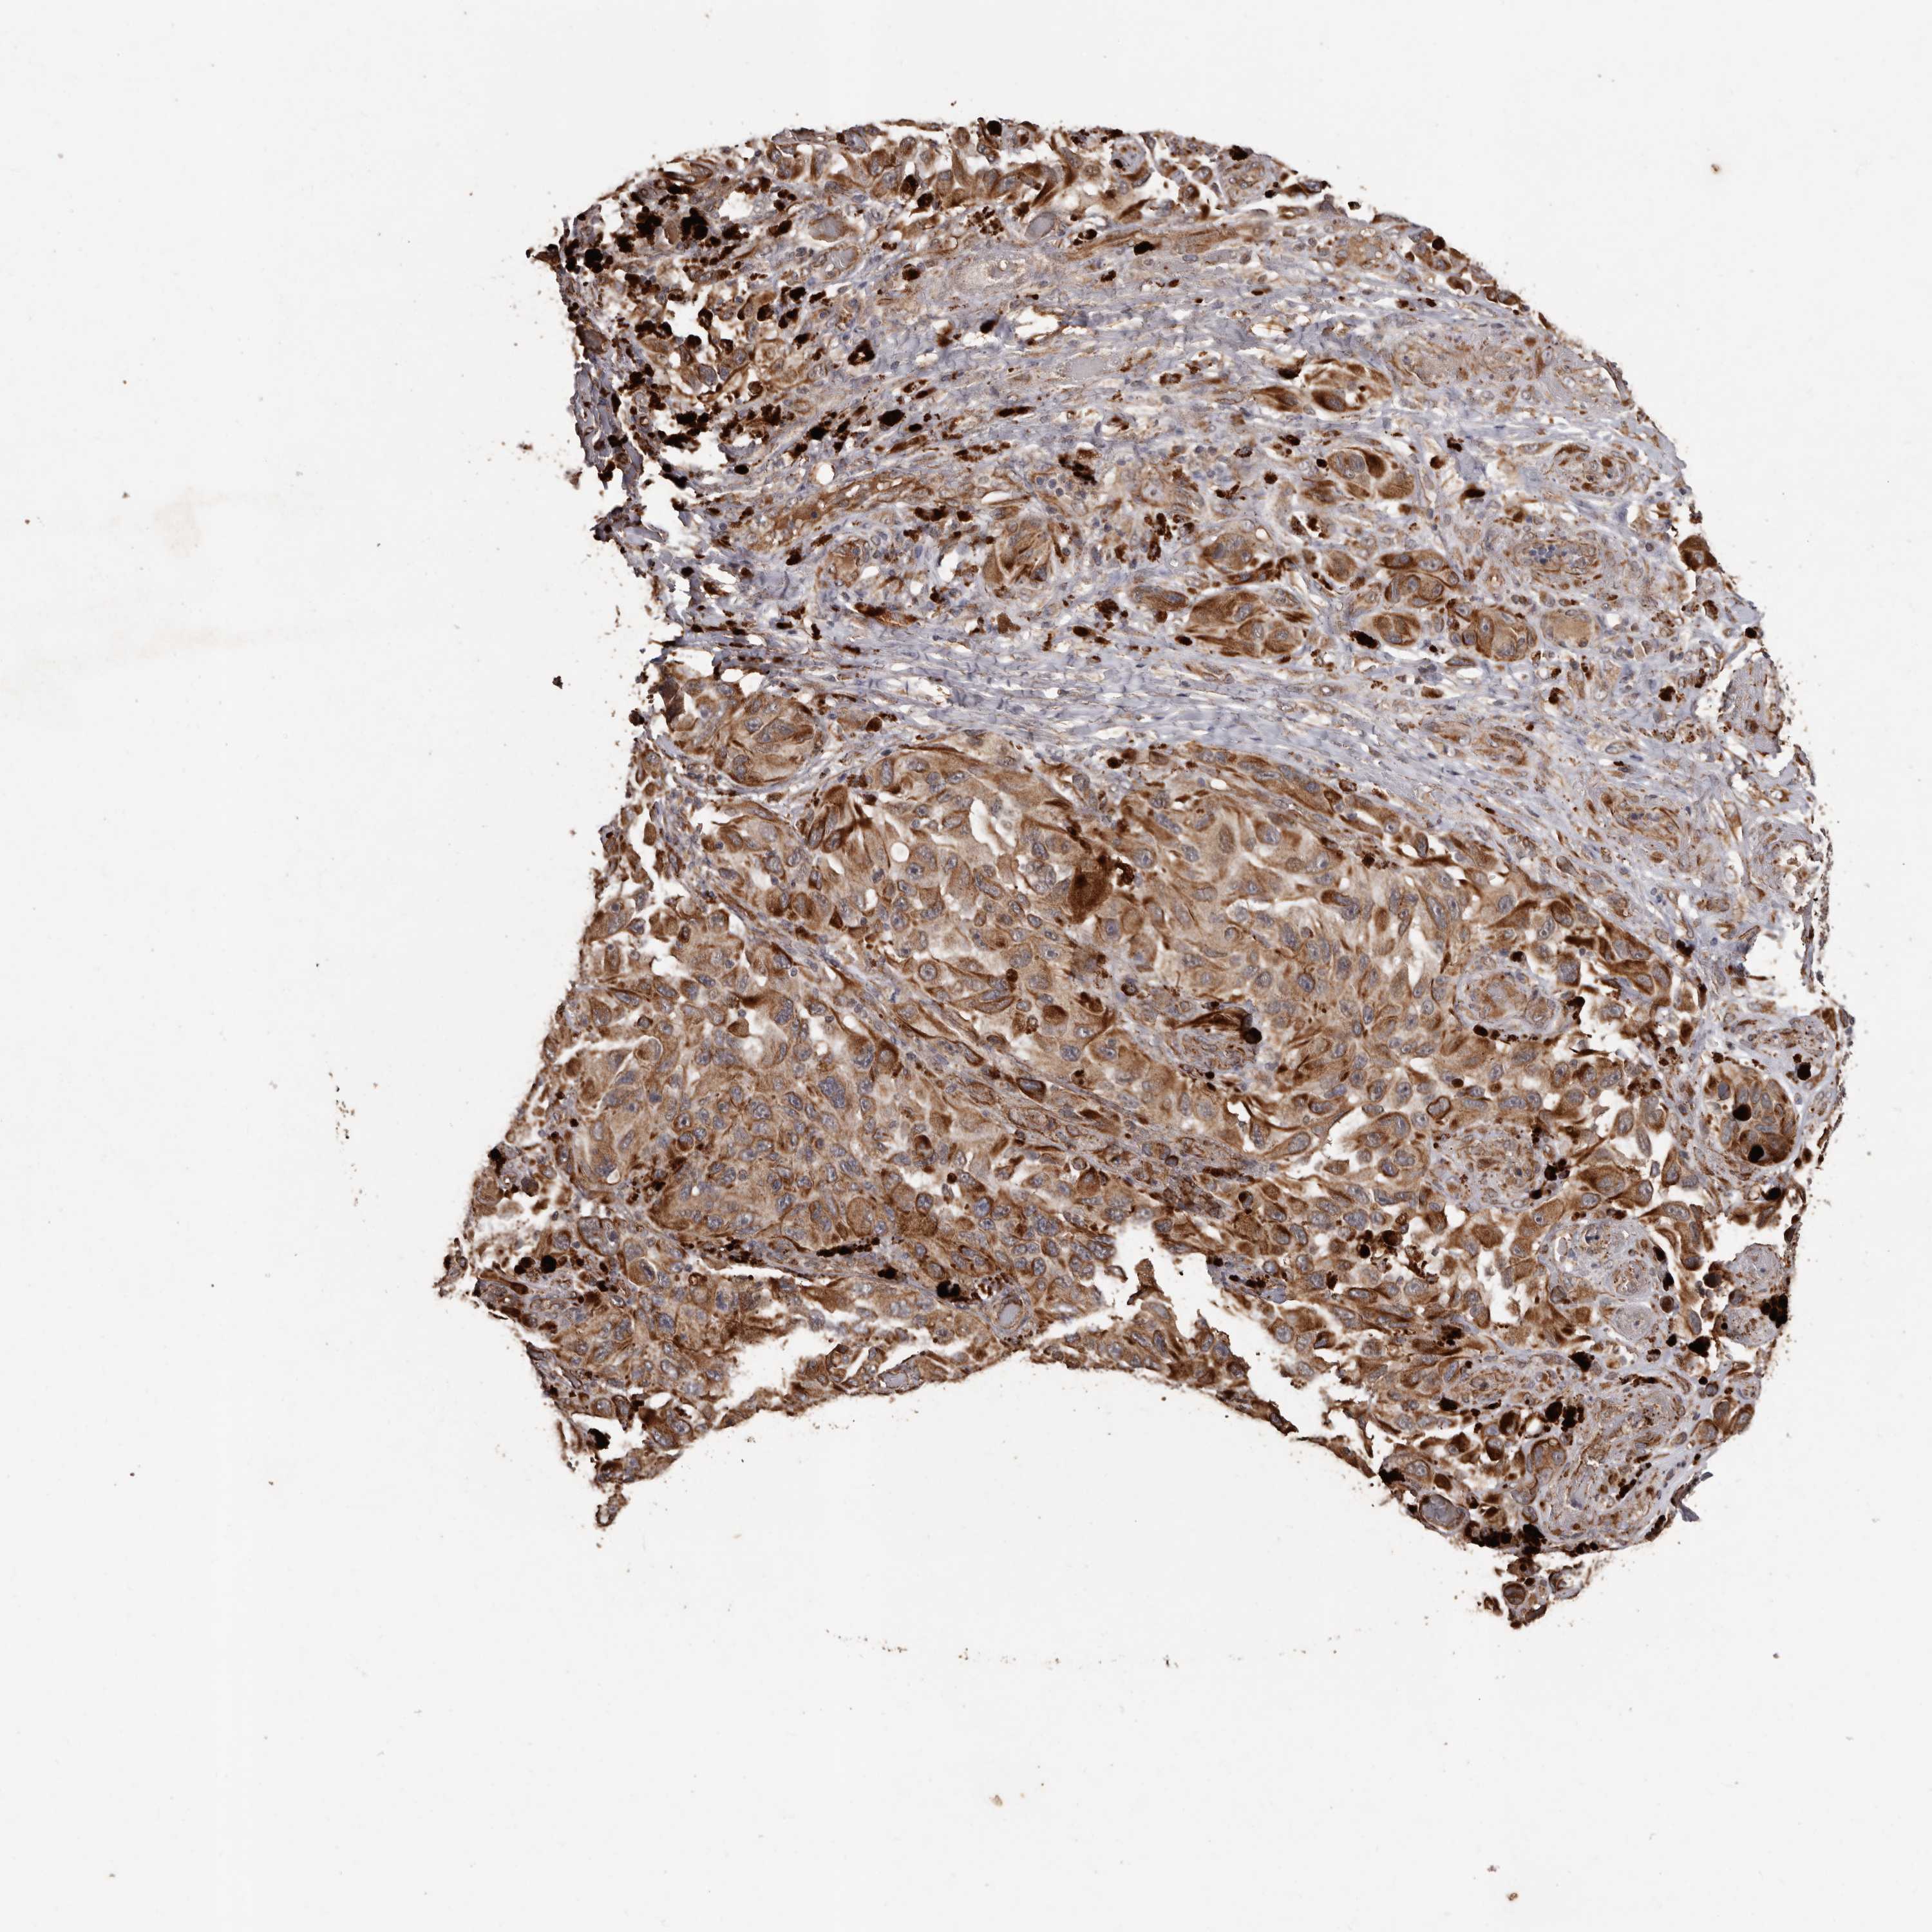

MELANOMA - Protein expressioni

A mouse-over function shows sample information and annotation data. Click on an image to view it in a full screen mode. Samples can be filtered based on level of antibody staining by selecting one or several of the following categories: high, medium, low and not detected. The assay and annotation is described here.

Note that samples used for immunohistochemistry by the Human Protein Atlas do not correspond to samples in the TCGA dataset.

Antibody stainingi

Antibody staining in the annotated cell types in the current human tissue is reported as not detected, low, medium, or high, based on conventional immunohistochemistry profiling in selected tissues. This score is based on the combination of the staining intensity and fraction of stained cells.

Each image is clickable and will lead to virtual microscopy that enables deeper exploration of all samples and also displays staining intensity scores, fraction scores and subcellular localization as well as patient and tissue information for each sample.

Antibody HPA029455

Staining

High

Medium

Low

Not detected

Intensity

Strong

Moderate

Weak

Negative

Quantity

>75%

75%-25%

<25%

None

Location

Nuclear

Cytoplasmic/membranous

Cytoplasmic/membranous,nuclear

Malignant melanoma, NOS

Malignant melanoma, Metastatic site